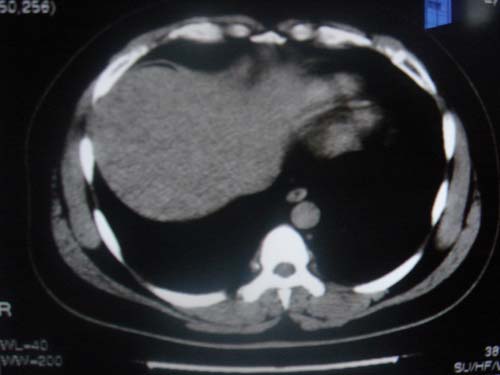

患者 男 40 右上腹不适 有胆囊息肉病史2年

本例就是胆囊比较大,内密度不很均匀,疑有砂砾状结石,未见息肉以及其他异常。

肝脏增大,

最后二副图像示胆囊壁增厚,与肝分界欠清,建议强化ct或磁共振

片中示肝脏的ct值低于脾脏,肝脏右叶外缘部份凹凸不平,考虑脂肪肝,肝硬化可能。结合其检查如b超或ct增强检查。

胆囊未见明显异常,肝脏密度似比脾脏密度低,测量一下ct值排除一下脂肪肝.当然做一下增强或mr就更好了.

肝右叶密度不均,脾大。强烈要求增强扫描除外浸润型肝癌。

肝大   密度降低  脾大  脂肪肝?